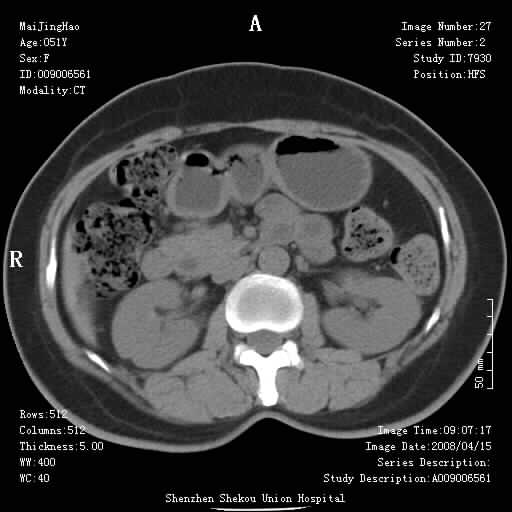

以下是引用余辉在2008-4-26 8:55:00的发言:[br]患者有结石史,此次腹痛4小时,胆总管全程扩张,应有胆总管末端梗阻,此次仍考虑胆结石症,积气不外两种原因,一种是结石下移时肠道内气体逸入,其次为产气菌感染。(倒数第三幅图像于扩张之胆总管末端似可见稍高密度影,考虑为结石影)

以下是引用听蝉观竹在2008-4-26 11:41:00的发言:[br]胆道手术分两种情况:[br]1、如果仅仅做胆囊切除手术,肝内胆管不会积气,只会出现胆总管代偿扩张,因为奥迪氏括约肌依然功能正常胆道与外界并不相通;[br][br]2、胆囊切除+胆总管空肠吻合手术(即roux-y式),则肝内胆管会出现积气,只是因为胆管与小肠相通,气体来源于小肠。这是临床十分常见的手术。[br][br]这个病例应该是胆囊切除+胆总管空肠吻合手术,是正常手术后表现,并不是胆道感染的表现。

以下是引用听蝉观竹在2008-4-27 10:10:00的发言:[br]关于胰头大小问题有几种测量方法和正常值:[br][br]1、直量法:横径<4cm;[br]2、胰头横径与相邻层面椎体横径的比值为二分之一,超过椎体横径就提示胰头增大;[br]3、正常组成年人肠系膜上动、静脉水平夹角正常值范围为4.9°~34.7°大于35°提示胰头增大。[br][br]上述方法只是一种具体的判断,是“量”的评估,更重要的是“质”的评估:一是观察边缘是否光滑,有无局部隆起,有无分叶;二是观察密度(增强,尤其在动脉期和门脉期)是否均匀。[br][br]所以对于胰头是否有异常不仅仅是是目测可以解决问题的,不要轻易就说“胰头增大”。还有一个问题就是测量胰头应该在增强ct上进行,这样可以避免将血管测量进去。[br][br]为什么啰嗦讲怎么多,因为我们实际工作中同样存在影像科医生和临床医生动不动就说胰头增大,说是胰头癌。大家看看是不是这种情况?[br][br] 我个人观点-----本病例的胰头不增大。[br][br][本贴已被 听蝉观竹 于 2008-4-27 10:12:41 修改过]